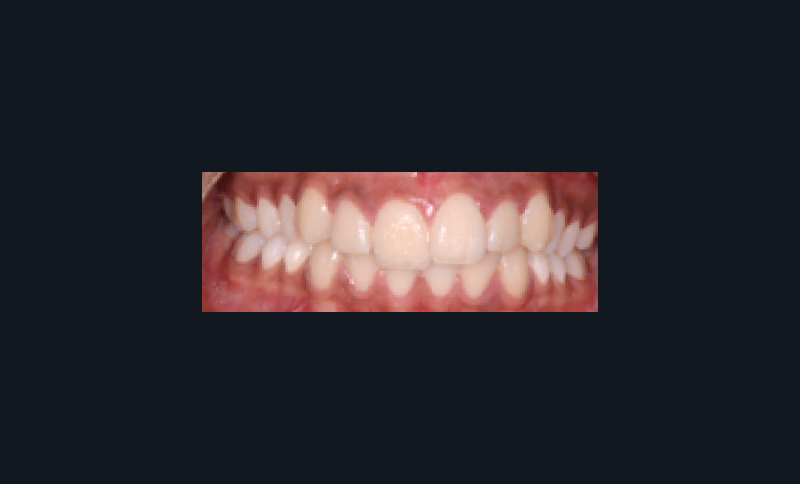

Examen clinique (fig. 1 à 7)

Sur le plan dentaire, elle présente une classe II d’Angle complète, une supraclusion de 4 mm et un surplomb de 6 mm ne correspondant pas au décalage de classe II molaire.